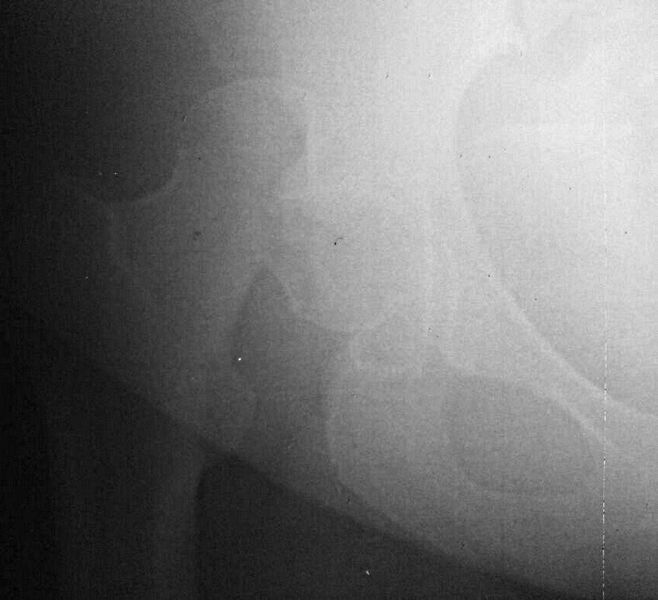

Через 12 дней выполнен остеосинтез головки 3-мя самокомпрессирующими винтами Герберта. Доступ Kocher-Langenbeck с флип-остеотомией большого вертела и задним хирургическим вывихом головки бедра. Интерпонирующий внутрисуставной фрагмент представлял собой лабрум с тонкой костной пластинкой от заднего края впадины. Фрагмент извлечен и фиксирован техникой spring-plate.

Обращал на себя внимание значительный дефект хряща головки бедра в нагружаемой зоне (как результат контакта головки с внутрисуставным фрагментом). Глубина повреждения хрящевого покрытия в центральной части дефекта достигает кости. Ничего не делали, расчитывая на замещение дефекта фиброзным хрящом. Промыли головку с впадиной, вправили вывих и ушились с активным дренажом.